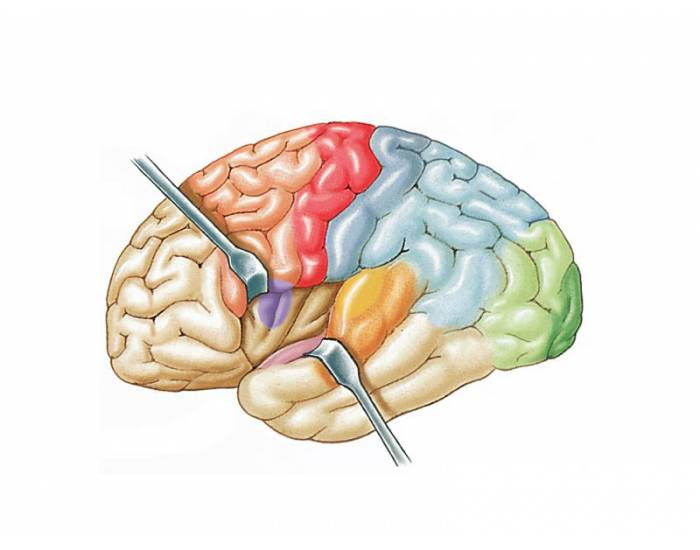

Схема чувствительных зон новой коры мозга